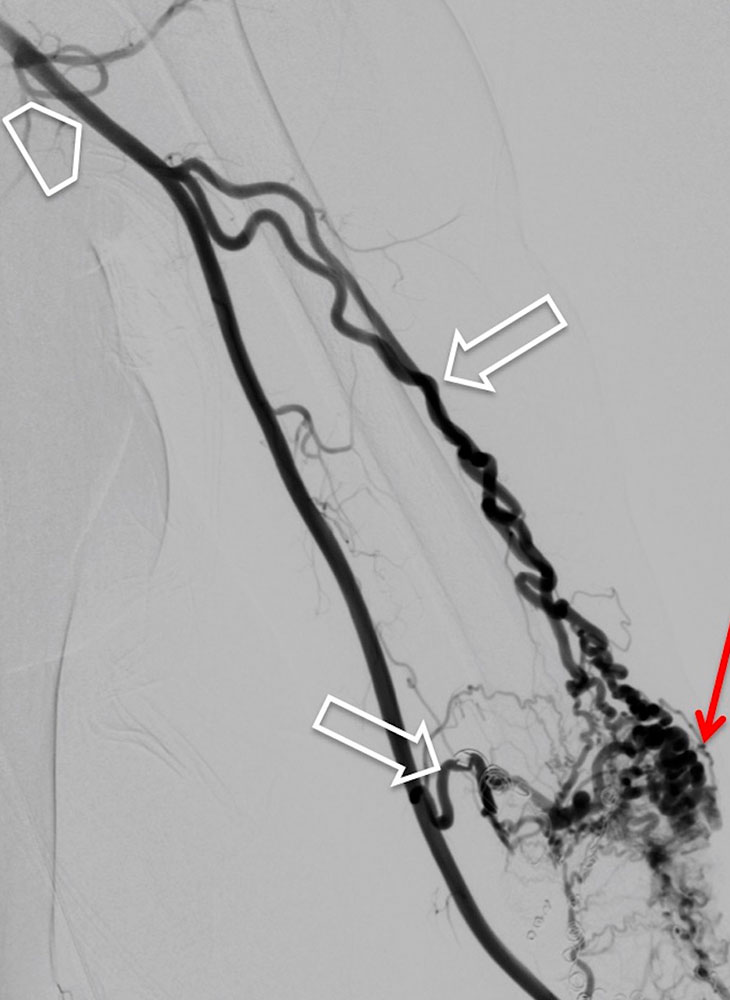

In most cases, catheter angiography is only performed as part of a minimally invasive treatment. The arteries supplying the nidus are often twisted, dilated and sometimes aneurysmally dilated. As a result of the arteriovenous shunt connections, there is immediate, early contrast filling of the dilated veins.

Peripheral arteriovenous malformations can be classified according to their angiographic anatomy, particularly their venous outflow.

Unlike venous malformations, there is characteristically no extensive contrast agent accumulation or contrast agent stasis in the form of "pooling". A so-called “blush” in the sense of a very fine fistulous nidus may appear at a very early stage of an arteriovenous malformation, for example in children, and this appears similar to a vascular tumor without a space-occupying mass.